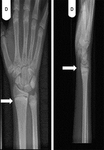

Punho direito de um paciente com raquitismo por deficiência de vitamina D antes do tratamento. Sua radiografia do punho direito revelou placas finais escleróticas e aumentadas do rádio e ulna (setas)

Seerat I, Greenberg M. Hypocalcaemic fit in an adolescent boy with undiagnosed rickets. BMJ Case Reports 2010; doi:10.1136/bcr.10.1136/bcr10.2008.1153

Punho direito de um paciente com raquitismo por deficiência de vitamina D depois do tratamento (setas)